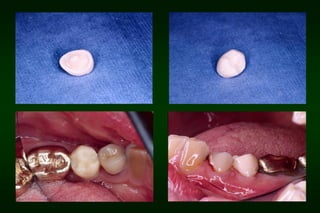

After 1 week

After 2 months